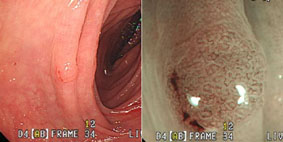

色素內視鏡(chromoendoscopy)是一種偵測腫瘤的利器,經由內視鏡噴灑專用色素後許多隱藏的早期腫瘤便無所遁形;病變組織染色後表面的紋路及形狀常可以幫助醫師當場判斷其性質、嚴重度、侵犯深度等等(圖1);本中心常使用碘化鉀(Lugol’s solution,用於食道)、indigocarmine、結晶紫(crystal violet)等染色劑。

最新的內視鏡科技:找出感覺不到的早期腫瘤(相關圖片)圖一. 左圖下方發現三顆扁平息肉;右圖為使用indigocarmine染色後息肉的形狀、輪廓、表面平滑度清晰可見。